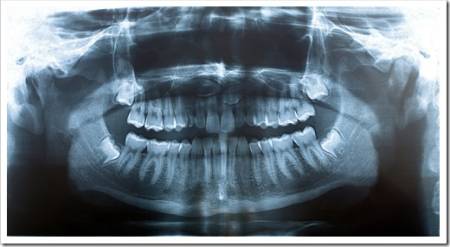

Панорамный снимок (или ортопантомограмма) – это плоское двухмерное изображение челюстей, зубов, гайморовых пазух и даже височно-нижнечелюстного сустава. Поскольку поверхность челюстей изогнутая, на плоской рентгеновской плёнке снимок отображается неравномерно увеличенным в боковых и передних отделах челюстей – то есть слегка деформированым.

- Много информации на одном снимке — видны все зубы с корнями, обе челюсти, гайморовы пазухи, височно-нижнечелюстные суставы, частично даже полость носа.

Панорамный снимок челюсти позволяет стоматологу получить изображение сразу всех зубов, включая верхнечелюстные суставы.

На рентгене отображаются зубные каналы, корни, костная ткань, пломбы и импланты.